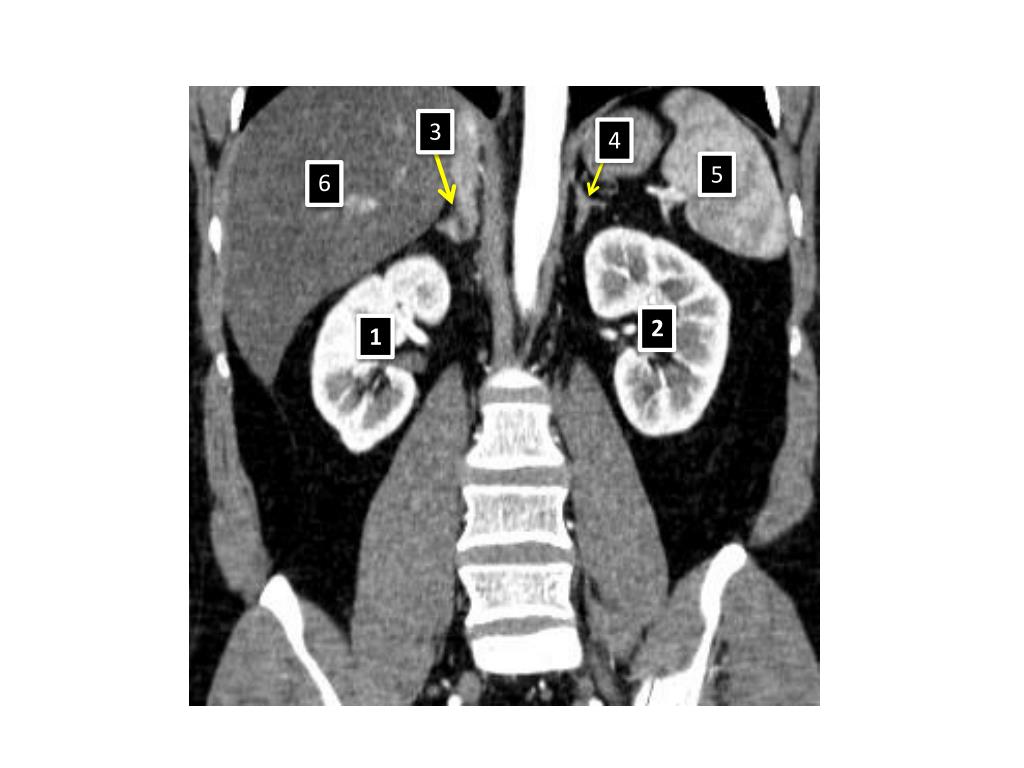

5. 3 4 5 6 1- Right kidney 2- Left kidney 3- Right adrenal gland 4- Left adrenal gland 5- Spleen 6- Liver 2 1